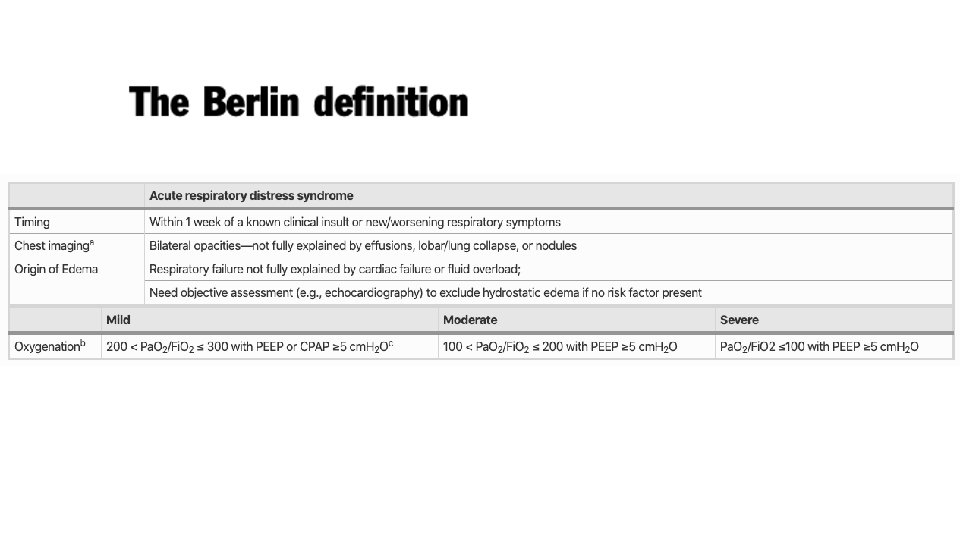

Acute Respiratory Distress Syndrome • Bernard GR, Artigas A, Brigham KL, et al. The American-European Consensus Conference of ARDS: definitions, mechanisms, relevant outcomes, and clinical trial coordination. American Journal of Respiratory and Critical Care Medicine. 1994; 149: 818 -824. • • • Acute Onset Bilateral Infiltrates on Chest x-ray Hypoxaemia Pulmonary Artery Occlusion Pressure <18 mm. Hg No validated diagnostic biomarkers are available

Acute Lung Injury <300 mm. Hg Pa. O 2/Fi. O 2 ratio Acute Respiratory Distress Syndrome <200 mm. Hg